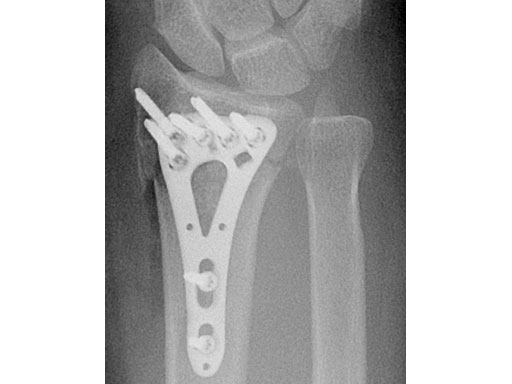

Fig 3ac Immediate postoperative x-rays.